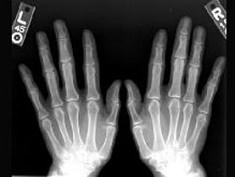

问题 女性,50岁,反复发作尿路结石,骨痛,骨骼X线示骨膜下皮质吸收。实验室检查:高钙血症,血清碱性磷酸酶↑,皮质醇抑制试验血清钙不下降。诊断考虑()

选项 A.原发性甲状旁腺功能亢进症 B.继发性甲状旁腺功能亢进症 C.三发性甲状旁腺功能亢进症 D.骨软化症 E.维生素D缺乏症

答案 A